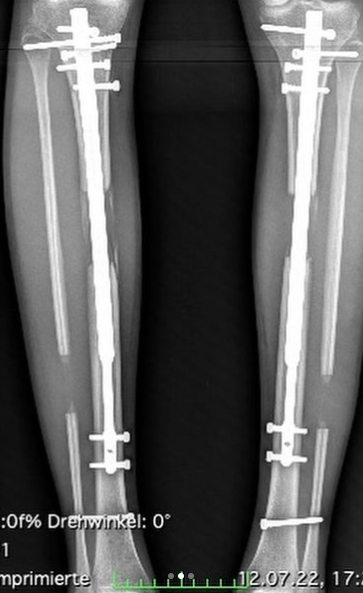

Bei der ersten OP "wuchs" sie um 8.5 cm, bei der zweiten um 5.5 cm. Alleine Thersias Beine sind nun 116 cm lang. Der Rest des Körpers wirkt auf den Bildern proportional zu klein. Die OP an sich könnte aus einem Horrorfilm stammen. Zuerst wurden Fischers Beine durchsägt und Teleskop-Stäbe eingesetzt. Mithilfe der Stäbe werden die Beine dann gestreckt.